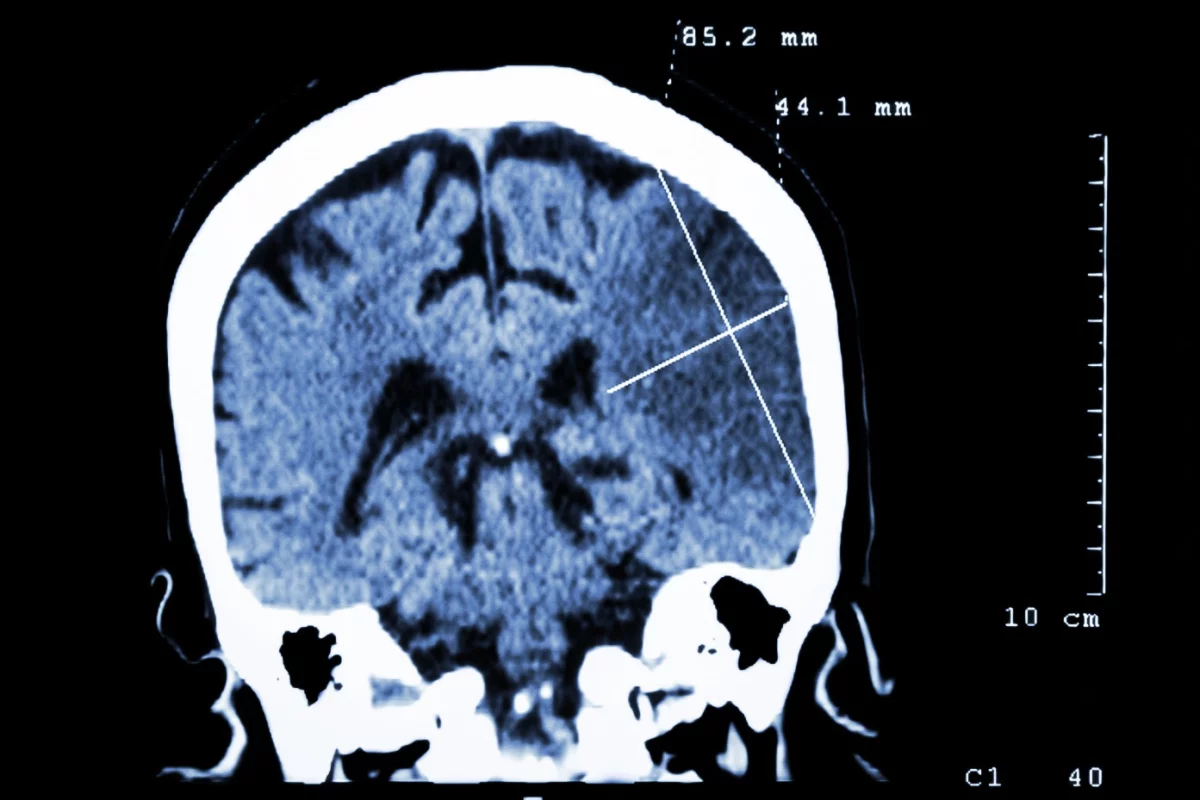

According to the American Stroke Association, stroke is the fifth leading cause of death in the US and one of the leading causes of adult disability. The death of brain cells due to lack of oxygen can result in, amongst other things, problems speaking, understanding speech and paralysis. Rehabilitation is a long, often lifetime, process, but researchers have found that a drug already used to treat certain conditions in humans can not only limit the effects of stroke, but also help repair the damage caused.

In a study involving rodents suffering stroke, researchers at the University of Manchester discovered that anti-inflammatory drug, interleukin-1 receptor antagonist (IL-1Ra), which is already approved for use in humans for the treatment of rheumatoid arthritis, limits the death of existing brain cells as well as promoting the birth of new neurons. The team found that there was a reduction in brain damage in rodents treated with IL-1Ra in the early stages after a stroke, while increased numbers of new neurons were found several days after the treatment.

While stem cell treatments have shown promise in studies for patients suffering the effects of a stroke, attempts to uncover drugs that can prevent initial brain damage after stroke have proven unsuccessful. So the fact IL-1Ra also appears to help the brain repair itself by generating new brain cells, with rodents regaining motor skills that were initially lost after stroke, is obvious cause for hope.